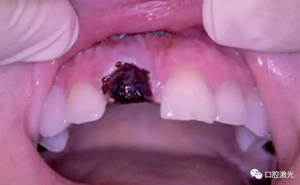

術(shù)后即刻

術(shù)后12周